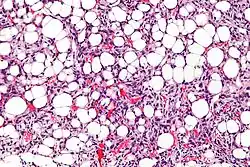

Jest to drugi co do częstości typ tłuszczakomięsaka, stanowi 40% przypadków tłuszczakomięsaków[1]. Do grupy zalicza się nowotwór dawniej osobno klasyfikowany jako tłuszczakomięsak okrągłokomórkowy. W 66% przypadków jest zlokalizowany w udzie, znacznie rzadziej w przestrzeni pozaotrzewnowej lub tkance podskórnej[1][11]. Zwykle są to dobrze odgraniczone wieloguzkowe guzy wewnątrzmięśniowe, koloru jasnobrązowego, o galaretowatym przekroju. Guzy są zbudowane z okrągłych lub owalnych prymitywnych mezenchymalnych komórek z wczesnych etapów lipogenezy i zmiennej liczby małych sygnetowatych lipoblastów w śluzowatym zrębie z charakterystycznym wzorem unaczynienia[1][12][11].